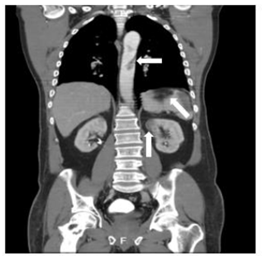

A los dos días el paciente se presenta con dolor abdominal y en pierna izquierda, por lo que se sospecha isquemia mesentérica y embolia a extremidad. Se realiza una angiotomografía de tórax y abdomen dónde se evidenció la presencia de ateromas calcificados incipientes con presencia de trombo en el arco aórtico distal y aorta descendente de 3,4 centímetros de longitud, mientras que en abdomen se documenta un infarto esplénico, del polo superior del riñón izquierdo y en extremidades se observa un trombo desde la arteria poplítea izquierda hasta el tronco tibioperoneo, reconstituyendo por colaterales (ver Figura 1 y 2 ).

Figura 1 Corte coronal angiotomografía de abdomen: la flecha superior indica el trombo en aorta. La flecha del medio indica el infarto esplénico. La flecha inferior indica el infarto renal.